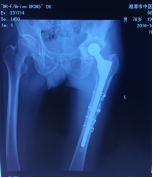

病例1 患者周某,女性,73歲,右髖關(guān)節(jié)置換術(shù)后15年,出現(xiàn)假體松動(dòng)并感染,在我院住院治療,關(guān)節(jié)假體感染翻修被稱為“關(guān)節(jié)外科醫(yī)生的終極挑戰(zhàn)”,老年骨科專家團(tuán)隊(duì)不畏艱險(xiǎn),應(yīng)用301醫(yī)院假體周圍感染翻修的先進(jìn)經(jīng)驗(yàn),采取二期翻修方案,整個(gè)治療分兩步進(jìn)行,第一次手術(shù)取出假體,清除感染,置入帶抗生素的骨水泥占位器,再進(jìn)行6個(gè)月左右的抗感染治療;感染控制后,再進(jìn)行第二次手術(shù),植入翻修人工關(guān)節(jié),并確保感染完全控制;患者經(jīng)過半年時(shí)間的治療,感染得到徹底控制,順利進(jìn)行了髖關(guān)節(jié)翻修手術(shù)。

術(shù)前資料

第一次手術(shù)后

第2次手術(shù)后